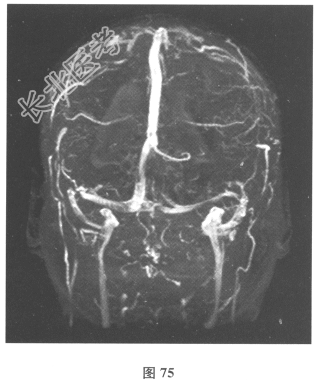

- 简答题3、患者入院后复查腰椎穿刺:脑脊液抗酸染色(-),墨汁染色(-),嗜酸性粒细胞比例增高,淋巴细胞体积较大。血及脑脊液弓形虫抗体均(-),血及脑脊液囊虫IgG抗体均(+),莱姆病抗体(-)。追问病史,曾经食用过“米猪肉”。进一步行颅脑MRI检查见图74、图75。)根据上述患者病史和检查结果,对此患者下一步治疗的药物包括